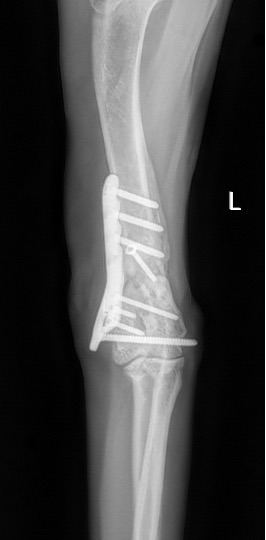

Exemple 2 :

Figure 4 : Pré-Op

Figure 5 : Post-Op Immédiat